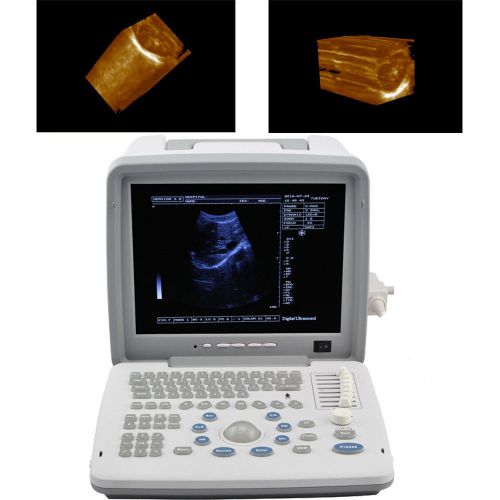

| 3D | 3D Ultrasound image working station |

12.1 CE LED Full Digital Portable Ultrasound Scanner + convex + 3D workstation

3D Portable Notebook Digital Laptop Ultrasound machine Scanner CONVEX PROBE

New 12.1 Full Digital Portable Ultrasound Scanner trans vaginal 3D workstation

3D Full Digital Portable Ultrasound Scanner convex & Transvaginal 3D workstation